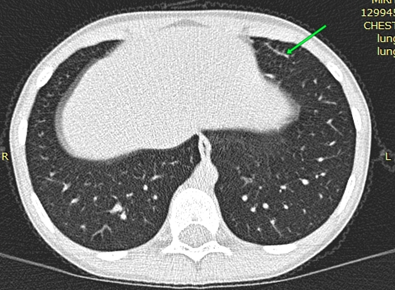

Рисунок 1 - MCКТ органов грудной клетки у ребенка Д

Примечание: стрелкой обозначен участок пневмофиброза в S5 слева (сагиттальный срез)

По результатам обследования: Общий анализ крови: Hb — 124г/л Э — 4,6·1012/л Л — 8,5·109/л п -0% с -27% э -22% б — 1% л — 41% м — 9% СОЭ - 4мм/ч. Эозинофилия относительная и выраженная абсолютная (1,87 × 10⁹/л, при норме до 0,5× 10⁹/л). Острофазовые показатели крови: АСЛО, СРБ, РФ — отрицательно. Биохимия крови: общий белок — 74г/л; глюкоза — 4,6ммоль/л, холестерин — 4,0ммоль/л, билирубин об. 10,1 мкмоль/л, прямой 2,4 мкмоль/л, ЩФ 153ед/л, железо 30,1мкмоль/л, ОЖСС 71,4мкмоль/л (норма 40–70). Признаки латентного дефицита железа. Иммуноглобулин Е общий: 1687 (норма до 90 МЕ/мл). Анализ крови на ИГЕ специфический: выявлена сенсибилизация к клещу домашней пыли, микст (Dermatophagoides Pteronyssinus, Dermatophagoides farinae, Euroglyphus maynei, Dermatophagoidesmicroceras, Acarus siro, Lepidoglyfus destructor, Tyrophagus putreus, Glycophagus domesticus) — 0,59 МЕ/мл, эпителию кошки 0,5 МЕ/мл, эпителию собаки 0,64 МЕ/мл (Норма до 0,5 МЕ/мл). ИФА на гельминты: антитела к а/г токсакар — отриц, а/г аскарид — отрицательно. Анализ крови на гуморальное звено иммунитета: lgA 1,70г/л, lgM 1,81 г/л, lgG 15,48 г/л. ЦИК 40 у.е. Анализ крови на фагоцитарное звено иммунитета: ФАН сп 54%, ст 70%, НСТ сп 42%,ст 60%, ФЧ сп 3,2ед, ст 4,10ед. Общий анализ мочи: цвет — с/ж, прозрачность — полная, плотность — 1015, белок — 0,122г/л (норма до 0,12г/л), лейкоциты — 1–2 в п/з, эпителий плоский ед.в п/зр. В цитологии носового секрета: лейкоциты 100–120 в п/зр (эозинофилы 98%). ПЦР мазка из зева: ЦМВ отрицательно; ВЭБ отрицательно, Герпес 6тип — положительно, Chl. pneumoniae — отрицательно, Мyc. рneumoniae — отрицательно. Бак посев из зева и носа: роста нет. По ЭКГ от 02.06.25: синусовая аритмия с ЧСС 73–107 мин. Нормальное положение ЭОС. Ускоренное АВ-проведение. По результатам оценки функции внешнего дыхания (спирометрия): исходно ЖЕЛ 97%, ФЖЕЛ 75%, ОФВ1 84%, МОС 25 – 90%, МОС 50–80%, МОС 75–80%. Нарушения проходимости трахеобронхиального дерева не выявлено. Результат пробы с бронхолитиком — положительно (прирост ОФВ1 на 16%). Уровень оксида азота в выдыхаемом воздухе — 48–64ppb (норма до 20 ppb). По УЗИ сердца: ВПС: открыты аортальный проток, компенсация. При проведении СКТ ОГК легкие расправлены. Легочный рисунок не усилен. Очагово-инфильтративных изменений не выявлено. Отмечается утолщение междолевой плевры на границе S4 и S6 сегментов правого легкого. Линейные пневмофиброзные изменения S5 левого легкого. Корни легких структурны, не расширены. Средостение не смещено, дополнительных образований не выявлено. Контуры диафрагмы четкие, ровные. Латеральные синусы свободные. Сердце обычных размеров. Костно-травматических и костно-деструктивных изменений на уровне исследования не выявлено. Мягкие ткани на уровне исследования без особенностей.